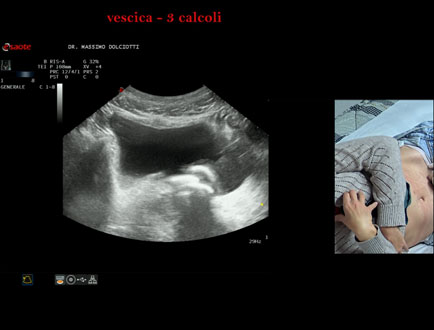

Data inserimento: 21/10/2025

Ecografia del: 15/10/2025

Strumento: Esaote MyLab Eight

Sonda: Convex Multifrequenza 1-8 MHz

Età Paziente: F 45 anni

Motivazione dell'esame: da alcuni mesi, disuria ed infezioni urinarie recidivanti.

Commento all'esame: le immagini ed il video documentano 3 immagini iperecogene, con cono d'ombra posteriore, da ricondurre a litiasi multipla della vescica.

Conclusioni: 3 calcoli della vescica (3 bladder stones).

Presentazione: Dr. Massimo Dolciotti - Ancona

Elaborazione digitale: Andrea Dini - Ancona